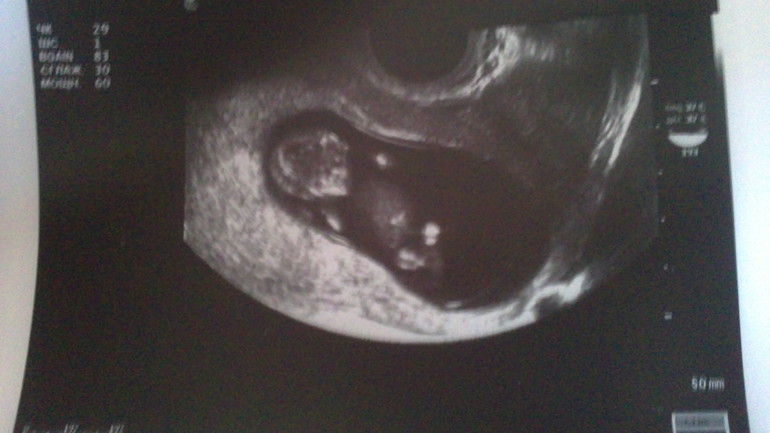

Когда на мониторе увидела свою кроху я чуть не расплакалась. Девочки ОН ТАКОЙ КЛАССНЫЙ ))) ножками и ручками дергает быстро быстро, УЗИстка даже сказала "Вон маме обрадывался, даже машет ей))" пыталась его сфоткать а он ну никак не дается, дергается постоянно) еле еле кое как фотку сделали. Вообщем поставила срок 10-11 недель (ктр 36), что развиваемся хорошо, ручки ножки наместе, сердечко бьется хорошо. Но пол пока не смогла увидеть да я и не расстроилась, главное что бы с малышом все хорошо. ))